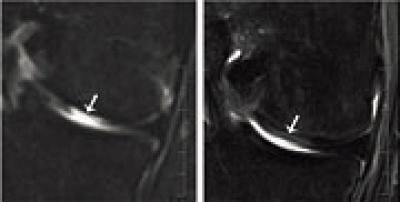

This figure shows an MRI of a defect tissue site before (left) and four months after (right) transplantation. Fig: University of Basel, Department of Biomedicine

Cartilage cells from the nasal septum (nasal chondrocytes) have a distinct capacity to generate a new cartilage tissue after their expansion in culture. In an ongoing clinical study, the researchers have so far taken small biopsies (6 millimeters in diameter) from the nasal septum from seven out of 25 patients below the age of 55 years and then isolated the cartilage cells. They cultured and multiplied the cells and then applied them to a scaffold in order to engineer a cartilage graft the size of 30 x 40 millimeters.

A few weeks later they removed the damaged cartilage tissue of the patients' knees and replaced it with the engineered and tailored tissue from the nose. In a previous clinical study conducted in cooperation with plastic surgeons and using the same method, the researchers from Basel recently already successfully reconstructed nasal wings affected by tumors.